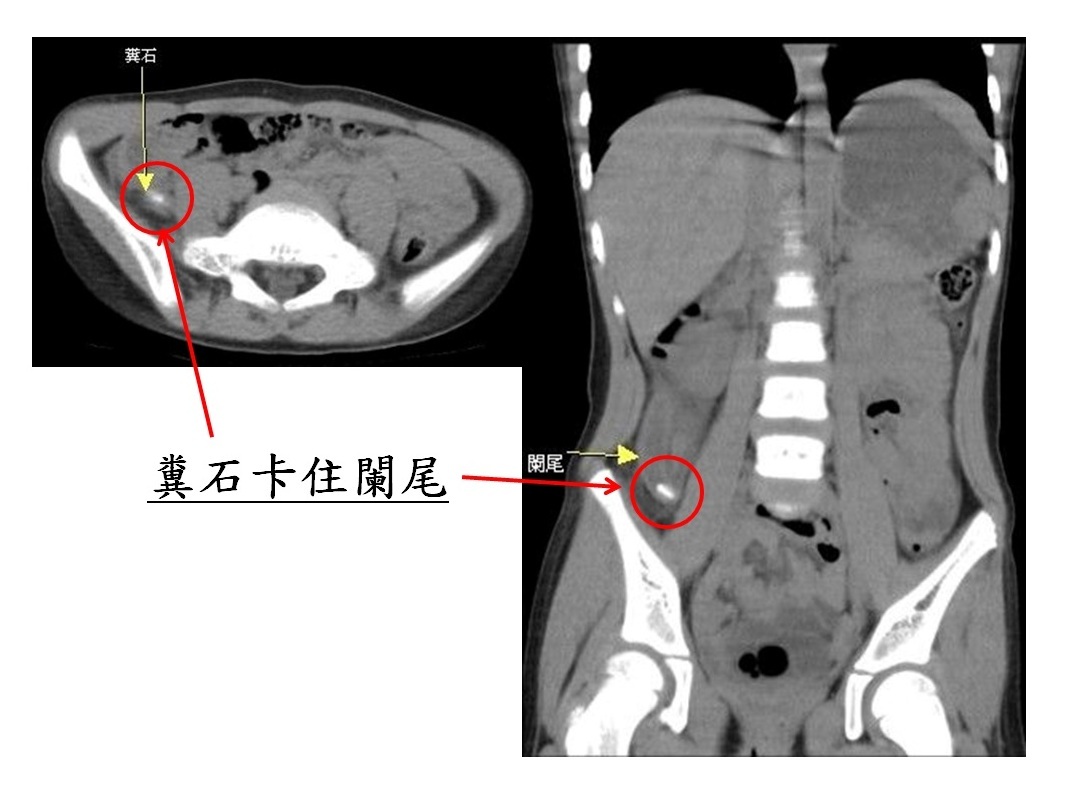

苗栗一名年僅4歲的小女孩,近日因出現嘔吐、腹脹及便秘等症狀,母親起初以為是一般腸胃炎或大便阻塞,並未立即帶她就醫。然而,隔天小女孩開始發高燒,並伴隨嚴重的腹痛,母親才緊急將她送往大千醫院急診。經醫師詳細檢查後,發現竟是糞石卡住闌尾,導致急性闌尾炎破裂,進而引發腹膜炎,情況相當危急。

▲ 病人經電腦斷層檢查,發現為糞石卡住闌尾(紅圈處),造成急性闌尾炎破裂合併腹膜炎。(圖/大千綜合醫院)

這起案例提醒我們,無論年齡大小,一旦出現不明原因的腹痛,應儘速就醫。馮啟彥主任特別強調,若延誤治療時機,可能導致腹膜炎及敗血性休克,不僅增加手術難度,也容易引發後遺症。